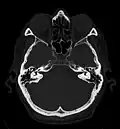

Das CT-Bild

In den ersten Jahren wiesen CT-Bilder in der transversalen Bildebene eine erheblich höhere Auflösung auf als in der sagittalen bzw. koronalen. Transversalschnitte waren daher damals die einzig sinnvolle Form der Bilddarstellung;[1] Radiologien befunden bis heute bevorzugt Transversalschnitte. Zur Orientierung: Der Betrachter blickt (vom Patienten aus gesehen) von unten auf einen Transversalschnitt, weshalb das, was aus Patientensicht links ist, sich im Bild rechts befindet.